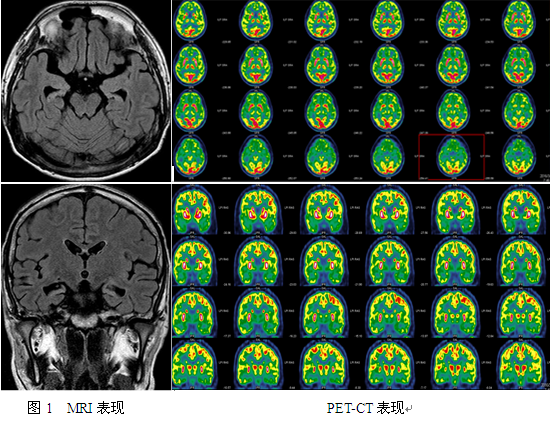

辅助检查:第一种类型(8):先兆→发声→右侧凝视→右眼睑强直→左侧强直-阵挛(面) →左侧偏转→双侧非对称性强直→GTCS. EEG:右半球。第二种类型(6):先兆→发声→快速眨眼→自动运动→强直-阵挛(头颈). EEG:左半球。MRI:1.弥漫性脑萎缩;2.双侧颞角扩大,双侧海马硬化;2.右侧颞上沟信号、双侧前扣带回信号增高(图1所示)。PET:双侧额叶眶回、直回、内侧面;双侧颞极、岛叶、颞叶内侧、顶中央盖低代谢;双侧颞叶新皮层(右著)低代谢(图2所示)。韦氏智力:全量表52,言语30,操作22,韦氏记忆<51。